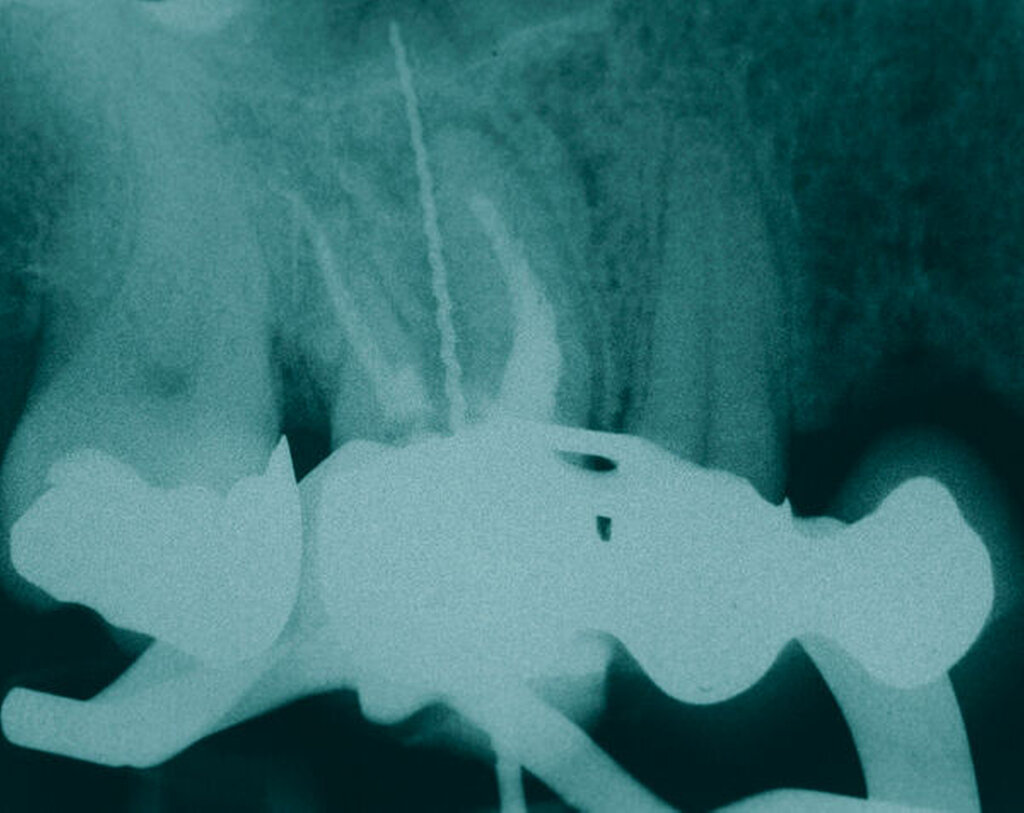

Längsfraktur der mesiobukkalen Wurzel (Fall Nr. 2)

Eine 46-jährige Patientin klagte 2014 über wiederkehrende Beschwerden an Zahn 16, die sich auch nach einer endodontischen Behandlung nicht besserten. Wiederholt waren submuköse Abszesse aufgetreten. Lokalisiert war die Sondierungstiefe stark erhöht, was auf eine Längsfraktur der mesiobukkalen Wurzel hindeutete. Die Patientin wurde über die Möglichkeiten der Amputation der mesiobukkalen Wurzel sowie alternativ der Extraktion des Zahnes aufgeklärt und entschied sich für den Versuch des Zahnerhalts mittels Teilamputation der mesiobukkalen Wurzel.

Im Rahmen der Versorgung erfolgte auch ein Austausch der Extensionsbrücke 16–14 durch Einzelkronen auf 16 und 15 sowie einer Implantatversorgung mit Einzelkrone in Regio 014. Der Erhalt des Zahnes 16 ermöglichte so eine wenig invasive Versorgung des ersten Quadranten mit guter Hygienefähigkeit. Alternativ wäre bei Extraktion des Zahnes die Versorgung beispielsweise mit einer ausgedehnten Brückenkonstruktion von 13–17 oder einem weiteren Implantat in Regio 016, vermutlich mit (indirektem) Sinuslift, notwendig gewesen. So konnte der Fall minimalinvasiv zufriedenstellend gelöst werden. Die Patientin ist seit dem Eingriff beschwerdefrei und kommt gut zurecht. Die Situation ist nun seit sechs Jahren stabil.